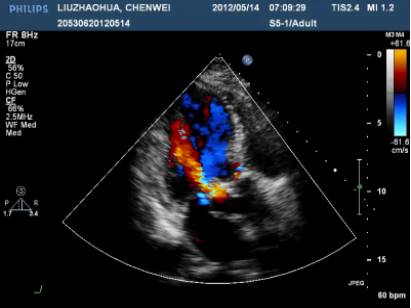

UCG示“主动脉瓣位生物瓣瓣架表面赘生物形成”,考虑“感染性心内膜炎”。

UCG“赘生物消失”,但停抗生素1周后再次发热伴寒战Tmax38.6℃UCG “主动脉瓣赘生物”。

主动脉瓣生物瓣赘生物;

瓣周漏。

UCG示“重度主动脉瓣瓣周漏,主动脉瓣中重度狭窄,各瓣膜未见赘生物”Coxiella burnetii抗体持续升高,提示感染持续存在。